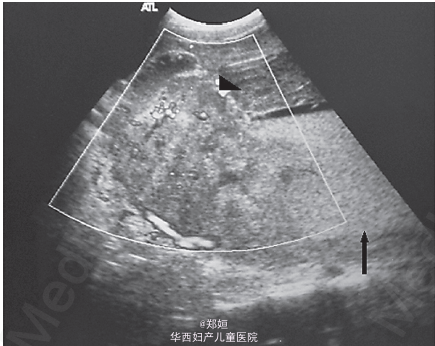

19岁女性,孕31周因剧烈腹痛就诊

体检发现腹肌紧张,宫高高于胎龄,可触及边界不清的肿块 临床怀疑为子宫肌瘤红色样变,胎盘肿块,胎盘早期剥离 超声提示胎盘显著增大 彩色多普勒提示胎盘肿块有血流信号 由于缺乏确切的临床和超声证据,采用MRI诊断 T1相可见肿块是异质的,而其余胎盘正常 肿块呈中间信号

MRI诊断为巨大的绒毛膜下血肿 由于患者血流动力学稳定,所以继续严密观察 孕32周行剖宫产 术中可见胎盘的巨大绒毛膜下血肿25*20cm